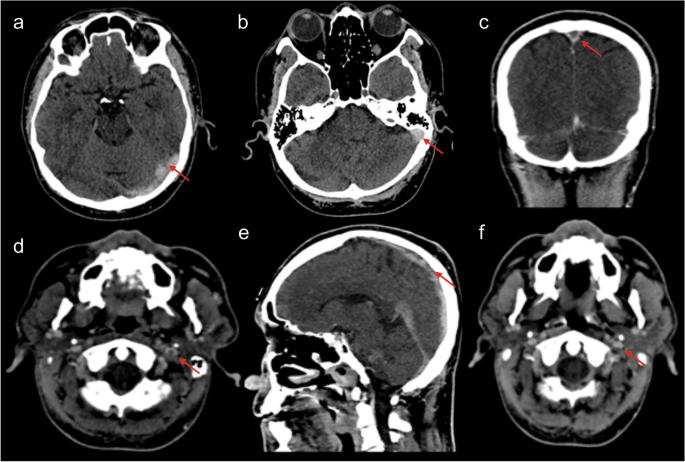

A noncontrast computed tomography (CT) of the brain showed cordlike hyperattenuation within the left transverse and sigmoid sinus suggestive of cord or dense clot sign (Fig. 1a,b). The patient elected to ignore the radiological finding and persevere with the symptoms. On March 22, he received the second dose of the vaccine (EP9605, Pfizer/BioNTech). Due to unresolved and somewhat worsening symptoms, the patient agreed to CT cerebral venography 2 days later. The finding confirmed a long segment-filling defect and empty delta sign within the superior sagittal sinus (SSS), extending into the torcula Herophili, left transverse sinus, and sigmoid sinus to proximal internal jugular vein (Fig. 1c,d). He was immediately started on therapeutic subcutaneous Clexane (1 mg/kg twice daily) and antiplatelet therapy (clopidogrel 75 mg). The autoimmune test and thrombophilia screening returned normal. The symptoms had gradually improved. Repeated CT cerebral venogram 2 weeks post-treatment shows residual cerebral VST (Fig. 1e). Filling defects within the proximal section of the superior sagittal sinus, left transverse sinus, and left sigmoid sinus were present (Fig. 1f). Opacification were visualized at the distal part of the superior sagittal sinus, torcula Herophili, and left internal jugular vein. Throughout these imaging techniques, no cerebral infarct or edema was seen. Following that, the clexane was switched to apixaban (5 mg twice daily).

Radiological finding. a, b The axial view of noncontrast CT scan brain shows hyperattenuation within the left transverse sinus and sigmoid sinus suggestive of cord sign (arrow). c The coronal view of CT cerebral venogram shows an empty delta sign with d axial view depicting a central filling defect in the proximal left internal jugular vein. Repeated CT venogram 2 weeks post-treatment in e sagittal and f axial view show residual dura venous thrombosis. There is presence of filling defect within proximal part superior sagittal sinus and well opacified left internal jugular vein